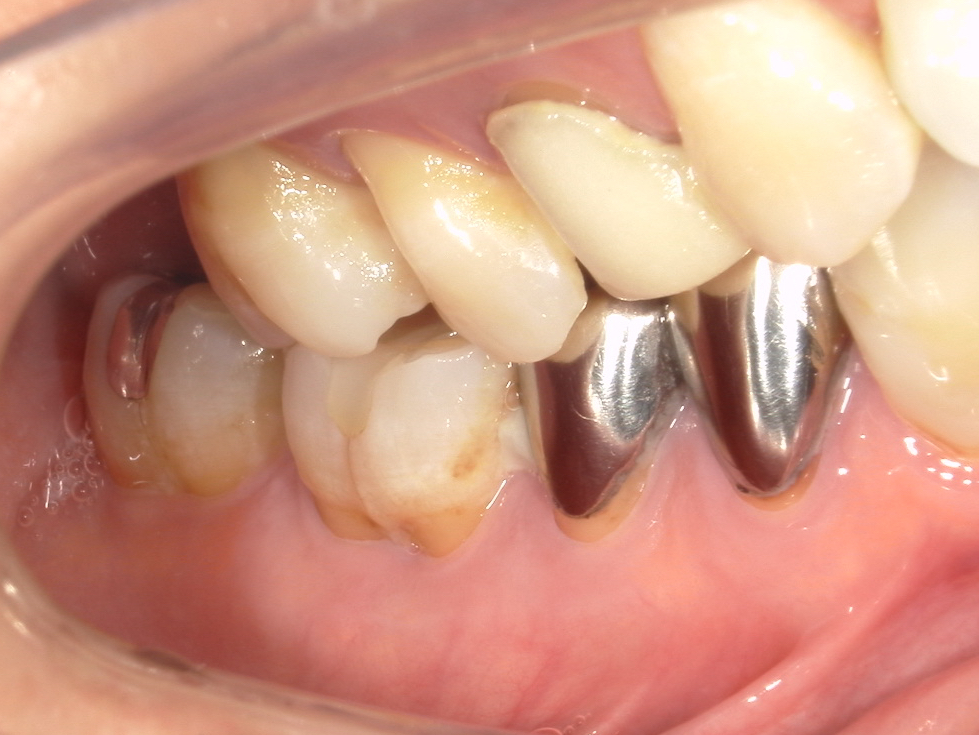

↑ブルーラジカル治療前

●主訴

右下2箇所腫れて歯茎下がってきた痛みなし

検診希望

●治療内容

右下5,7 ブルーラジカル処置

●年齢

60代

●性別

女性

●目的

ブルーラジカルで歯を残したい